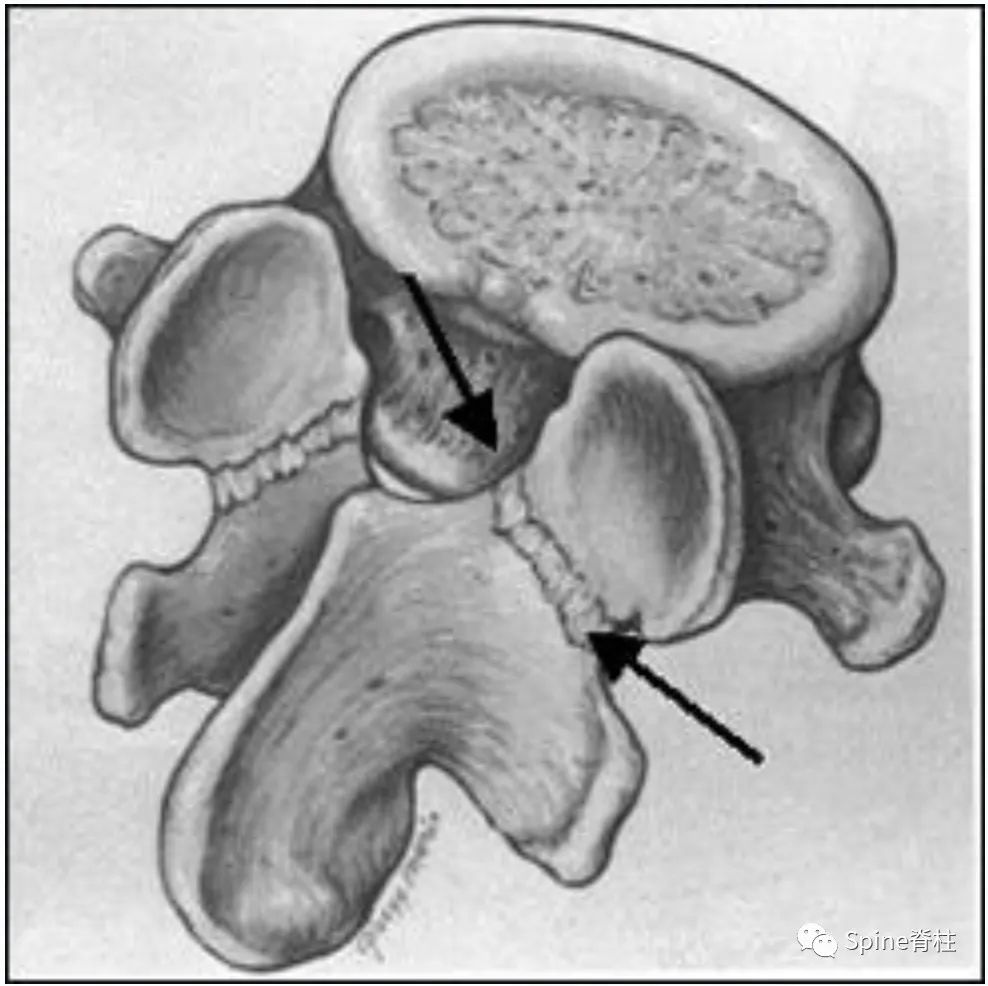

从生物力学角度分析,峡部处于一个承受剪切应力的位置,前后方向的外力 (可引起滑脱)试图使上关节突相对于同一节段下关节突前移时就会形成剪切应力。因此,常见的峡部裂就是上关节突、椎弓根和椎体作为一个整体向腹侧移动,而下关节突与后方的椎弓保持连接。

峡部是在相邻节段平移运动中承受应力最大的部位, C2和L5的峡部最易发生创伤性或应力性骨折 (如C2的hangman骨折和L5峡部裂) 。峡部构成椎管侧隐窝的后部,并参与构成神经根管的后壁。